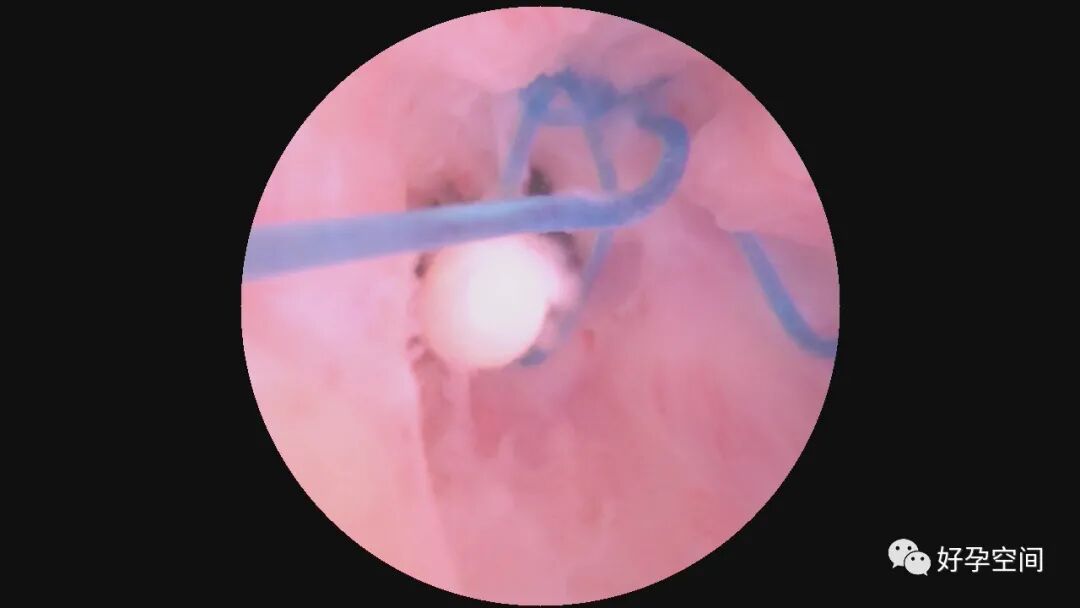

病例4:30岁,G2P1,剖宫产1次。本次停经40+天,计划外妊娠。一次性宫腔镜见胚胎着床于宫腔左后壁,约3cm*3cm*2.5cm,摘除胚胎后宫腔形态正常,双侧输卵管开口可见。